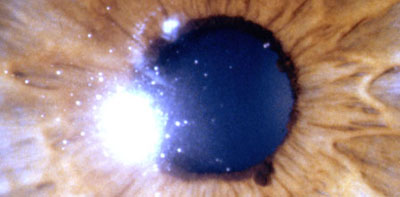

Aniridia completa, catarata y distrofia corneal de la aniridia

Archivo Dr. Francisco Barraquer

Caso de paciente con Coloboma en un ojo y Aniridia en el contralateral

OD

Archivo Fotográfico Dr. Francisco Barraquer

OI

Archivo Dr. Francisco Barraquer